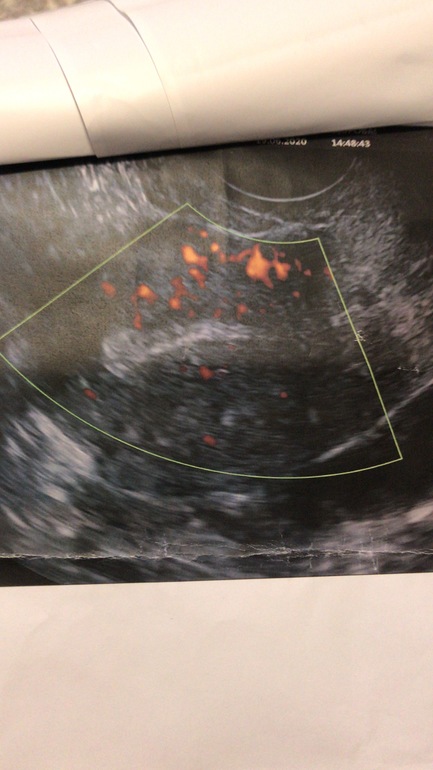

Я сначала ходила на Пиявки с 5-6дц, на след цикл на физио с 6дц. Совмещать нельзя. Вот вам мой результат кровотока до и после) Думаю разница огромная. И я верю в Пиявки , они действительно помогли, кто бы что не говорил.